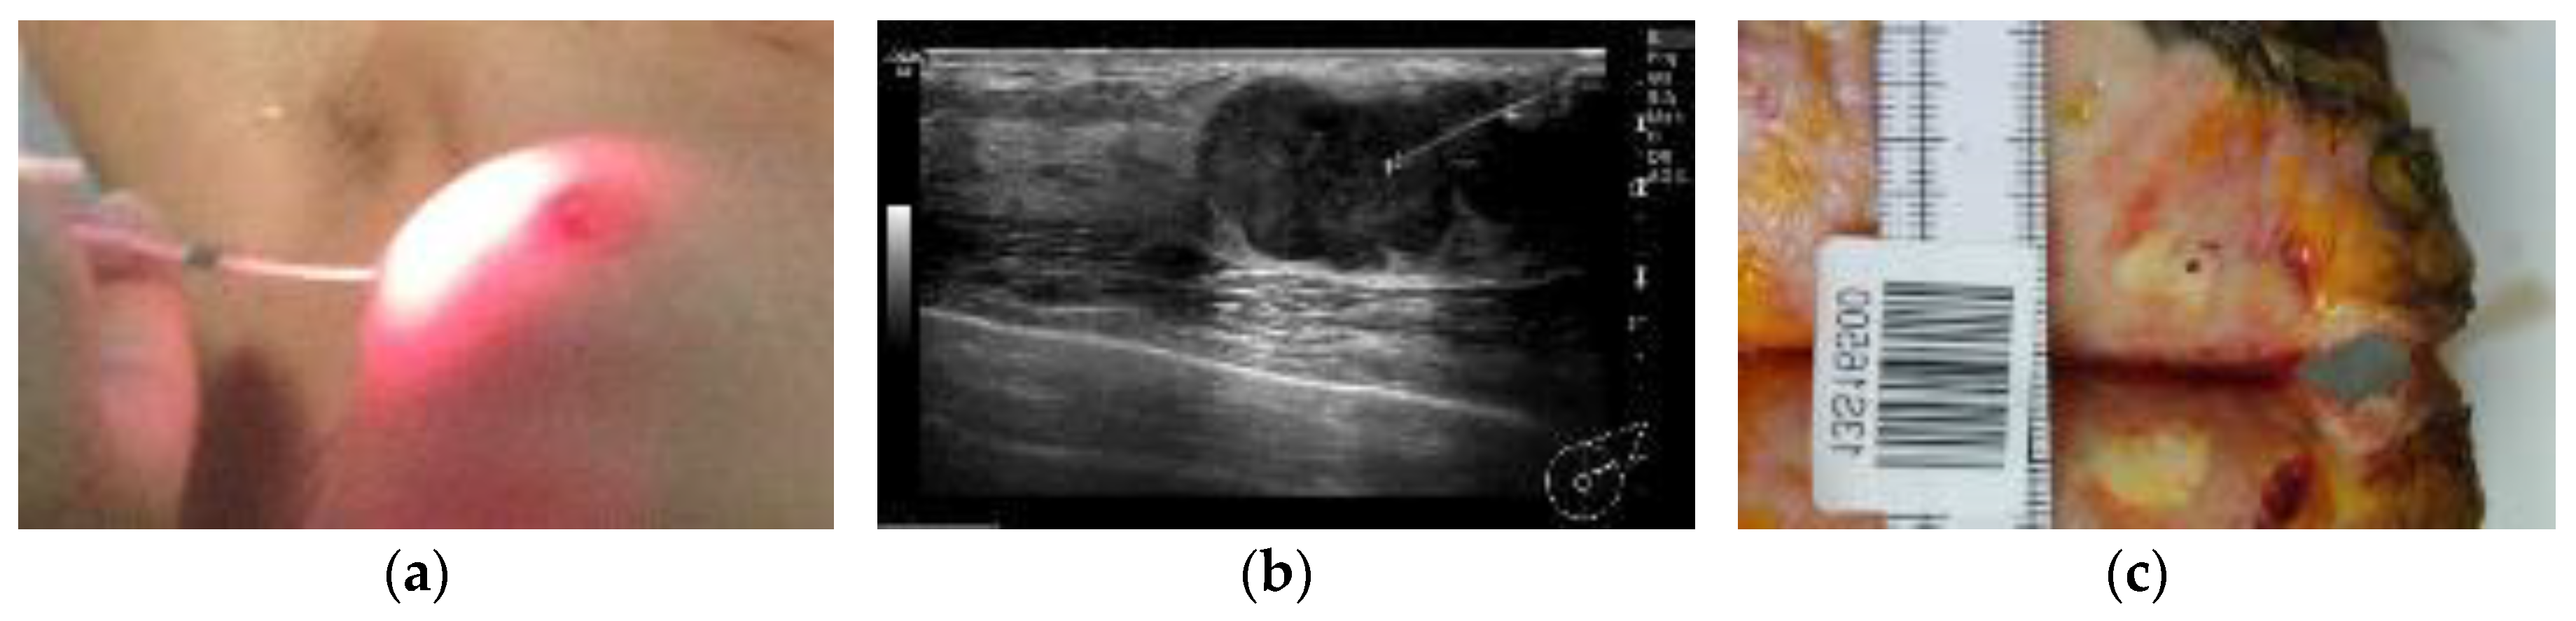

2.3. Photodynamic Therapy